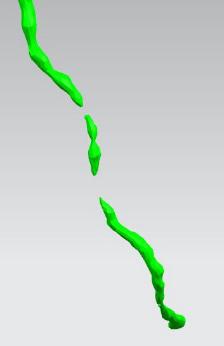

首先通过病人的心脏冠脉造影CT数据,获取病人的心脏冠脉三维模型。

病人的冠脉造影CT数据 提取出的冠脉三维数据

其次在对应的病灶位置进行一定的细节修改,或改变其形状或改变颜色以便于突出显示病灶位置。

模型细节修改